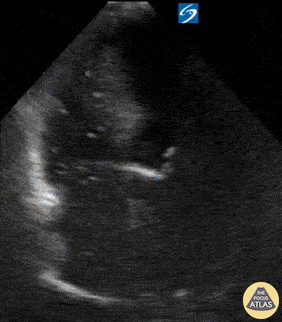

Pictured here is an apical four chamber view of the heart in a patient who presented for evaluation of dyspnea and was found to be in atrial fibrillation with RVR. POCUS is most notable for the presence of gas bubbles throughout the right atrium and right ventricle. Symptoms of venous air embolism can range from asymptomatic to cardiovascular collapse and death. The presence of venous air embolism may occur due to head or neck surgery, chest trauma, hemodialysis, central vein cannulation, high pressure mechanical ventilation, or thoracentesis. Rupinder Sekhon, MD & Peter Biggane, MD Central Michigan University, Emergency Medicine